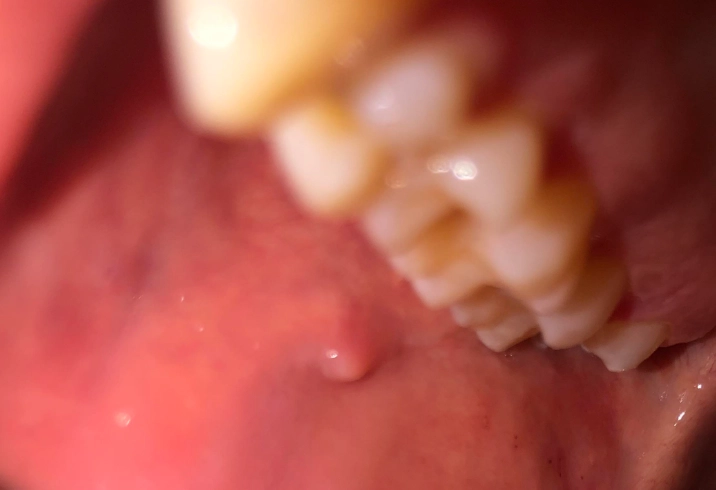

Fibroma

This is the body's overzealous response to chronic irritation. If you have a habit of chewing on your cheek, a rough tooth, or an ill-fitting denture rubbing in the same spot, your body might lay down extra fibrous tissue as a “callus.” The result is a fibroma. What it feels/looks like: A firm, smooth, pink lump. It's like a little dome-shaped knot of scar tissue. It's anchored down and doesn't move much when you push it. Completely benign and very, very common.